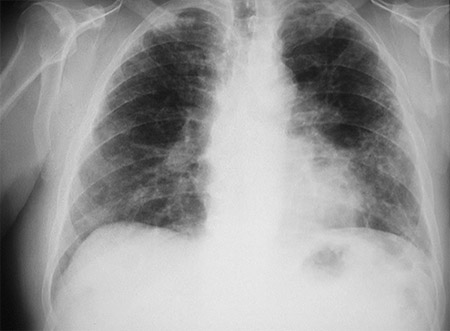

Aparência da asbestose à radiografia torácica: presença de fibrose intersticial linear na zona inferior, envolvendo progressivamente todo o pulmão, com espessamento pleural.

[Figure caption and citation for the preceding image starts]: Radiografia torácica para asbestoseDo acervo pessoal do Kenneth D. Rosenman, Michigan State University [Citation ends].